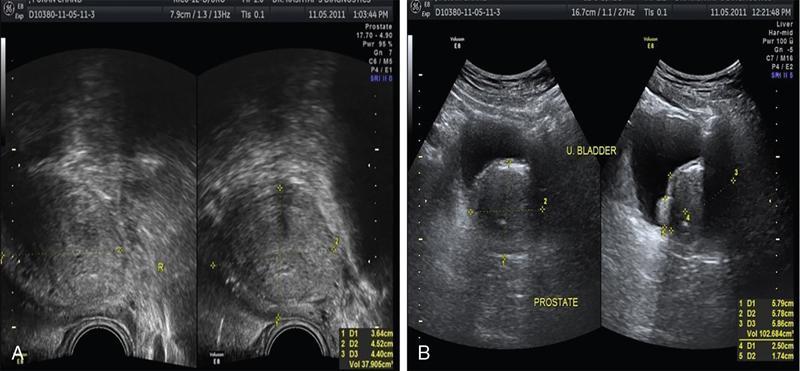

ULTRASOUND MALE PELVIS Vivek Kashyap Pelvic ultrasound is a noninvasive technique for imaging major organs in the pelvis including the bladder, prostate gland, blood vessels and bowel. It is usually the first line of investigation to evaluate the prostate and seminal vesicles. Ultrasound is a safe and reliable imaging resource to assess the pathology and guide towards appropriate treatment plan. To start pelvic ultrasound with evaluation of the shape and size of the bladder. The bladder is in the pelvis, posterior to the pubic bones. The peritoneum is seen superior to the urinary bladder and reflecting over the anterior surface. The trigone is a triangular area bounded by the two ureteric and urethral orifices. The urinary bladder has an outer loose connective tissue layer, known as subserosa which bounds the three muscular layers. The innermost is the mucosal layer. These layers should be smooth and uniform and the thickness will depend on the bladder distension. Prostate can be seen posterior to the urinary bladder when examined in transverse views. Prostate is seen at the inferior part of the urinary bladder in sagittal view (Fig. 11.1.1.1A). It should be examined in both the views. Urinary bladder neoplasms are usually seen arising from the walls of the urinary bladder, though these can be of varying shapes, usually are polypoidal and can present as solitary or multiple lesions, often seen on opposing walls of the urinary bladder, also known as ‘kissing lesions’ (Fig. 11.1.1.1B). For evaluating the bladder, it should be moderately filled. An overfilled bladder will cause patient discomfort and can compress structures posterior to it. The bladder should be scanned in the transverse and sagittal planes and prevoid volume is calculated. After micturition, the length, width and height (cm) of the bladder are recorded in sagittal and horizontal planes. The postvoid residual volume is calculated using the formula: Postvoid residual volume (PVR) = Length × Width × Height × 0.5 Normally there is no residual urine. PVR less than 50 is usually considered as insignificant. PVR volume more than 100 mL is considered significant in adults. Ureteric jets are the normal visualization of the physiological periodic efflux of urine from the distal ureter into the bladder. Ureteric jet can be appreciated by colour Doppler examination as a sudden burst of colour in the bladder that lasts for a few seconds. Bladder wall thickening is considered significant if >3 mm in a distended bladder and >5 mm in a collapsed bladder; however, it’s a good practice to fill the bladder completely before doing the investigation (Fig. 11.1.1.2). The common causes of bladder wall thickening include: Urinary bladder diverticula are examined very well on ultrasound (Fig. 11.1.1.2). Congenital diverticula, also known as Hutch diverticula are generally seen near the ureteral orifices. Acquired diverticula are generally due to bladder outlet obstruction. Bladder mucosa herniates through weak portions of the bladder walls, this may create diverticula with a narrow neck leading to urinary stasis, which may in turn cause stones, infection tumours or ureteric obstruction. These diverticula appear as an outpouching sac from the bladder and urine may be seen flowing into or out of the diverticulum. Intraluminal pathologies such as vesicle calculus are seen within the bladder, calcifications are seen in the bladder wall or in the mass lesions. Faeces, inflammatory or neoplastic bowel lesions, enlarged lymph node, masses from nerves, vessels and bones, ectopic or transplant kidney, accessory spleen can also be diagnosed from pelvic ultrasound. Ultrasound use for the male pelvis even though limited, has great importance to detect free abdominal fluid, undescended testes in the groin and hernias. Dilated urethra in posterior urethral valves, and occasionally a valve itself can be seen in real-time sonography, aided by transperineal scanning. Prevoid and postvoid volume Wall thickness Ureteric jets Size and volume Morphology of central and peripheral zone Morphology of seminal vesicles ULTRASONOGRAPHY INGUINOSCROTAL REGION V. Sivakumar Ultrasonography is the ideal noninvasive imaging modality for evaluation of scrotal abnormalities. It is capable of differentiating the most important aetiologies of acute scrotal pain and swelling, including epididymitis and testicular torsion, and is the imaging modality of choice in acute scrotal trauma. In patients presenting with palpable abnormality or scrotal swelling, ultrasonography can detect, locate and characterize both intratesticular and extratesticular masses and other abnormalities. A 12–17 MHz high-frequency linear array transducer provides excellent anatomic detail of the testicles and surrounding structures. In addition, vascular perfusion can be easily assessed using colour and spectral Doppler analysis. In most cases of scrotal disease, the combination of clinical history, physical examination and information obtained with ultrasonography is sufficient for diagnostic decision making. This review covers the normal scrotal anatomy as well as various testicular and scrotal lesions. Ultrasound is the widely used modality of choice for evaluation of scrotal abnormalities. Scrotal ultrasound is very helpful differentiating the most common causes of acute scrotal pain and swelling, including epididymoorchitis and torsion testis, and is the choice of investigation for acute scrotal trauma. Detection, localization and characterization of intratesticular and extratesticular pathologies are made easy using scrotal ultrasound. A 12–17 MHz high-frequency linear probe or transducer provides valuable anatomical information of testes and adjacent structures. Colour and spectral Doppler analysis can be used in assessing the vascular perfusion status of scrotal structures in real time. In most cases of scrotal disease, the combination of course, clinical history, clinical examination and imaging finding on ultrasound and Doppler is very essential in the diagnosis of scrotal diseases. Clinical examination sometimes leads to nonspecific signs and symptoms such as vague scrotal pain, suspicious scrotal mass or swelling. In such situations, ultrasound is useful in diagnosing and characterizing intratesticular and extratesticular pathologies as well as distinguishing benign or malignant lesions as well as identifying conditions requiring emergency surgical attention. Scrotum is a fibromuscular sac like structure divided into two hemiscrotum, right and left by a midline septum or raphe. Both the testes are located within the scrotum. The normal testicle appears like a ovoid structure with a homogeneous intermediate echogenicity and measuring approximately ~ 5 × 3 × 2 cm (craniocaudal, anteroposterior, width) (Fig. 11.1.2.1) Epididymis is elongated comma-shaped structure abutting posterior margin of testes and divided into three parts, head, body and tail. Epididymal head is seen in close relation to superior pole of testis and appears iso- to hyperechoic to the adjacent testicular parenchyma (Fig. 11.1.2.2). Epididymal body and tail can be visualized posterior to and along inferior pole of the testes and appears isoechoic to testicular parenchyma. A separate fibrous capsule called the tunica albuginea in each of the hemiscrotum encloses the testes and epididymis. This fibrous capsule can be noticed as a thin echogenic band like structure surrounding the testis on ultrasound. Tunica albuginea is covered by the tunica vaginalis, which is a remnant of processus vaginalis. It represents a closed sac of peritoneum and has two layers. The visceral layer of tunica vaginalis is seen lining the tunica albuginea of testis and is separated from the parietal layer that lines the inner aspect of the scrotal wall by minimal fluid-containing interspace. The tunica albuginea extends into the posteromedial aspect of testis to form the mediastinum testis (Fig. 11.1.2.3). It contains ducts, nerves and blood vessels. On ultrasound mediastinum is noticed as a thin echogenic band like structure. There are numerous fibrous septa extending from mediastinum testis dividing the testicle into multiple small lobules. The lobules are made of seminiferous tubules, they converge to form the tubuli recti, which are the testicular ducts that open into the rete testis. In around 20% of population, the rete testis can be visualized as a hypoechoic area adjoining the mediastinum testis. Efferent ductules coming out of rete testis can be seen draining into the epididymal head. From epididymal head, the ducts converge into a single duct in the epididymal body and exit the epididymal tail as the vas deferens. The vas deferens runs along the contents of spermatic cord and courses superiorly within the inguinal canal. The spermatic cord contains nerves, testicular artery, deferential artery, cremasteric artery, lymphatic ducts and the pampiniform venous plexus. On ultrasound the spermatic cord appears as an echogenic band like structure within the inguinal canal. The major vascular supply to the testes is by the paired testicular arteries which arise from the abdominal aorta. The testicular artery after entering into the tunica albuginea branches into capsular arteries and recurrent rami branches which then courses centrifugally into the mediastinum. A collateral circulation comprising of deferential artery and the cremasteric artery is also seen. Arterial supply to the remaining parts of the scrotum is from the pudendal arteries, which arise from the internal iliac artery. Anatomic relationships of the vascular structures within the spermatic cord are important and alteration in this normal relationship is associated with few pathologies. High insertion of tunica vaginalis to the spermatic cord, the bell-and-clapper deformity leaves the testes to rotate freely within the tunica and can lead to intravaginal testicular torsion. The pampiniform venous plexus continues as the testicular vein in the deep inguinal canal. The right testicular vein drains directly into the inferior vena cava (IVC) whereas the left testicular vein drains into the IVC via the left renal vein. Epididymal and testicular appendages usually represent embryologic remnants. They are better visualized in ultrasound in the presence of a hydrocele. The appendix of testis (hydatid of Morgagni) can be visualized as an isoechoic, oval structure between the epididymis and testis (Fig. 11.1.2.4). An appendix of epididymis is a pedunculated structure arising from the epididymal head, which is also isoechoic to testicular tissue. Ultrasound of the scrotum includes both greyscale and colour Doppler evaluation of testicles, epididymis on both sides and the scrotum. Spectral Doppler evaluation can be used to demonstrate normal waveforms in the testicular artery and vein. For scanning a high frequency, broad bandwidth 17–5 MHz or 12–5 MHz linear array transducer is used. With the help of a towel placed under the scrotum the testicles and scrotum are elevated. With another towel the patient retracts and covers his penis. Initially with a side-to-side large-field imaging both testes are demonstrated using both greyscale and Doppler techniques. Echogenicity and perfusion of each testis is examined. Each testis is imaged longitudinally in medial, mid, lateral portions and transversely in upper, mid and lower pole regions. Three-dimensional (3D) measurement of each testicle is taken (length, width and height). Epididymis evaluation includes longitudinal and transverse imaging including head, body and tail. Colour Doppler study of testes and epididymis is done on both sides and status of capsular and centripetal arteries assessed and documented. Spectral waveform of both arterial and venous flow is documented on each side. Optimization of colour and spectral Doppler analysis is done to clearly depict low velocity venous flow. Colour Doppler imaging in various planes and comparison with contralateral asymptomatic testis is done in specific evaluation for testicular torsion. Scrotal survey should be done for extratesticular findings such as hydrocele, varicocele or calcification/scrotolith. The pampiniform plexus of veins should be evaluated for the diameter and its augmentation on standing position or Valsalva manoeuvre. Scrotal wall should be assessed for thickening and oedema. Extratesticular and intratesticular pathologies, either focal or diffuse should be identified and characterized using grey scale and Doppler imaging techniques appropriately. Focal lesions should also be measured three dimensionally. Presence of solid, cystic, calcific, complex cystic areas in the lesion should be characterized. Labelling of the lesion/images in respect to location (upper, middle or lower), orientation (longitudinal and transverse) and position of the patient (supine, decubitus and standing) is done. Labelling of the lesion/images during specific manoeuvres such as Valsalva should also be done. For scanning a high frequency, broad bandwidth 17–5 MHz or 12–5 MHz linear array transducer is used. Initially with a side-to-side large-field imaging both testes are demonstrated using both greyscale and Doppler techniques. Echogenicity and perfusion of each testis and epididymis should be examined. Each testis is imaged longitudinally in medial, mid, lateral portions and transversely in upper, mid and lower pole regions. Epididymis evaluation includes longitudinal and transverse imaging including head, body and tail. Spectral waveform of both arterial and venous flow is documented on each side. Ultrasound and colour Doppler are the first-line imaging modality for acute or chronic scrotal pathologies. Ultrasound is a safe and reliable imaging modality for demonstration of scrotal anatomy, localization of testicular pathologies and for assessing the vascularity. Since most of the testicular pathologies have characteristic ultrasound appearance, ultrasonography is able to clearly guide patient management and prevent unnecessary surgery. TRANSRECTAL ULTRASOUND OF PROSTATE Vivek Kashyap Carcinoma prostate is the second most common cancer in the world and the sixth leading cause of cancer death in men. The worldwide burden of prostatic cancer is estimated to touch 1.7 million new cases and 499,000 deaths by 2030. The prostate is an unpaired glandular organ. The average dimensions in a healthy young adult is 3.75–4.00 × 2.5–3.00 × 3.1–3.8 cm (w × h × l) and the volume ranges from 20–25 cm3. It produces the prostate-specific antigen (PSA) a glycoprotein which is an ingredient of the semen and is responsible for liquefying semen. The prostate has endocrine properties as it produces prostaglandins E, F and A, spermidine and spermine. It is also the place of the conversion of testosterone into dihydrotestosterone under the influence of the 5-α-reductase enzyme. COMMON INDICATIONS FOR A TRANSRECTAL ULTRASOUND (TRUS) OF PROSTATE Assessment of prostate size Abnormal growth within the prostate Male infertility Elevated PSA levels Detecting disorders within the prostate Micturating difficulties Because ultrasound provides real-time images, it can be used to guide biopsies which may be necessary, FNAC or tissue biopsy as well as brachytherapy seed placements. Transrectal US is a widely used clinical imaging method. For confirming the diagnosis of prostatic cancer, a systematic needle biopsy with US guidance is the diagnostic test of choice (Fig. 11.1.3.1). To understand the images produced by transrectal US, it is important to understand the zonal anatomy of the prostate gland. The outer zone is the peripheral zone, inner to it the transitional zone, then central zone and periurethral zone. The peripheral zone is the largest, containing almost 70% of the prostatic tissue and is the site of most prostatic cancers. It is separated from inner zones by a surgical capsule which may be seen as hyperechogenic line The transitional zone is much smaller (about 5%) and is seen as two small glandular areas such as saddle bags adjacent to proximal urethral segment. The central zone constitutes almost 25%–30% of the total gland size. The ducts of vas deferens and seminal vesicles pass through this zone. This zone shows only about 5% incidence of cancers and appears relatively resistant to diseases. The periurethral zone is only about 1% and encircles the urethra. The commonest features of benign prostatic hyperplasia are hypoechoic enlargement of inner zone. Other features could be calcifications along with diffuse or well-circumscribed rounded hypoechoic or hyperechoic nodules along with degenerative or retention cysts (Fig. 11.1.3.2A,B). Well-circumscribed hypoechoic nodules arising in the transitional zone may become so large that they distort the gland and appear to be in the peripheral zone and these are invariably benign. In cases of hyperplastic nodules occurring in the peripheral zone, they will appear as firm to hard nodules and should undergo a biopsy. We must remember that prostatic enlargement may not correlate with urinary symptoms in all cases, therefore any urinary dysfunction calls for evaluation of the prostate, bladder, urethra, spine and CNS. Transvesicle ultrasound is done to evaluate prostate size, median lobe, bladder trabeculations, diverticula, tumours or calculi. Patients who have had TURP done before will invariably show a defect in the gland. However, the size of the defect will not always correlate with the amount of tissue removed during the procedure, nor does it correlate well with the success of the procedure. This is a condition of inflammation of the prostate and seminal vesicles. The prostate may appear normal in prostatitis or there may be a focal mass, ejaculatory duct calcification, irregularity or thickening of the capsule, periurethral glandular irregularity, dilated periprostatic veins and distended seminal vesicles. Chronic granulomatous prostatitis can present as diffuse large or small hypoechoic zones or a solitary hypoechoic lesion. The examination is generally painful and colour Doppler may show a very vascular focus (Fig. 11.1.3.3A). If we see a hypoechoic mass within the prostate with or without internal echoes may be an abscess. Common ones are degenerative or retention cysts in hyperplastic nodules. These are generally symptomless, unless they become large (Fig. 11.1.3.3B). Prostatic utricle cysts are in the midline and are caused by dilatation of prostatic utricle. These can be associated with unilateral renal agenesis and rarely contain spermatozoa. Other type of cysts seen are Mullerian duct cyst which are a little lateral and are also tear drop and do not contain spermatozoa. Ejaculatory duct cysts are small and could be a small diverticulum of the ejaculatory duct or an obstruction. These can be fusiform in shape with pointed ends and contain spermatozoa. These are associated with infertility. Seminal vesicle cysts are another type, which could be large and solitary, associated with ipsilateral renal agenesis sometimes. In cases of male infertility, transrectal sonography has an important role in assessment of causes of azoospermia for ejaculatory duct obstruction or anomalies (about 1%–2%) Seminal vesicles, dilated ejaculatory ducts and midline cysts can suggest obstruction. There is a strong association of absence of vas with cystic fibrosis. The results of transrectal scanning in infertile men with azoospermia can be normal appearance (25%), bilateral absence of vas deferens (34%), bilateral occlusion of the vas, seminal vesicles or ejaculatory ducts by calcification or fibrosis (16%), unilateral absence of vas (11%), obstructing cysts (9%), ductal obstruction due to calculi (4%). Some of these causes, more so in distal two-thirds could be surgically correctable and therefore it is essential that careful evaluation is done. Haematospermia is blood in the semen. This could be acute (red in colour) or dark brown (old blood). Nonspecific inflammation of the prostate or seminal structures is the most common cause, resolving on its own after some time. We should exclude tumours or infection of prostate or bladder. Transrectal scanning can detect calculi or cysts in the seminal vesicles or ejaculatory ducts (Fig. 11.1.3.4). Other causes includes vascular malformation or sometimes following a prostatic biopsy. Ultrasound elastography is an imaging technique for mapping tissue stiffness of the prostate gland. Two elastography techniques that have developed are strain technique, and second, shear wave technique. The tissue stiffness information provided by US elastography can improve the detection rate of prostate malignancy and provide guidance for biopsy. Prostate elastography has high sensitivity for detecting prostate malignancy and shows high negative predictive values, ensuring that few malignant lesions will be missed. Transrectal US has been used for local staging of prostate cancer in some studies but is generally considered insufficient. Extracapsular extension (ECE) can be demonstrated by the bulging or irregularity of the capsule adjacent to a hypoechoic lesion. Seminal vesicle invasion (SVI) is diagnosed by demonstrating the extension of a lesion at the base of the prostate into a seminal vesicle. Solid hypoechoic lesions within the seminal vesicles or asymmetry of the seminal vesicles are indirect indicators of disease extension. Additional transrectal US-guided biopsies of the seminal vesicles can be performed when extra prostatic extension into the seminal vesicles is suspected. Studies performed in the 1980s showed when cancers are larger (stage T3) and more readily palpated, sensitivity for detecting ECE and SVI by transrectal US was more than 80%. With advent of colour duplex and power Doppler US, there has been renewed interest in the use of transrectal US to identify cancer in hyper vascular areas, with only modest improvements in sensitivity and specificity. Transrectal US continues to play an important role in therapy for directing brachytherapy seeds into the accurate location within the prostate. Cryotherapy and focal ablation of the prostate cancer also requires transrectal US guidance. Future developments in transrectal US may include the utilization of microbubble contrast agents and targeted imaging. Microbubbles coated with surface ligands that preferentially target tumour neovascularity can be used. Because of the large size of these bubbles (1 m), these agents can provide information about large-vessel microvascularity which can be useful in detecting cancer; however, if in future smaller-size microbubbles are available, they can further improve detection. Seminal vesicles have symmetric appearance and lie cephalic to the prostate and posterior to the bladder. They have a typical ‘bow-tie’ appearance in transverse scans, and a club or tennis-racket shape in longitudinal scan. They show homogenously fine echoes but less echogenic than prostate. Volume of seminal vesicles tends to shrink after the fifth decade. TRUS provides excellent anatomical details of seminal vesical and ejaculatory ducts. TRUS helps to diagnose calculi in seminal vesicle or ejaculatory duct. Also TRUS provides high-resolution imaging of the prostate, seminal vesicles and vas deferens and is the investigation modality of choice in diagnosing congenital and acquired abnormalities implicated in the cause of obstructive azoospermia. USG FEMALE PELVIS M. Alamelu Ultrasound is a noninvasive, easily available and informative investigation. A skilfully done and well-interpreted ultrasonogram image usually obviates the need to proceed to additional expensive and composite cross-sectional imaging tests. Ultrasound is high-frequency sound waves (20 kHz), inaudible to human that can be safely transmitted into human body to scan the tissues. Images produced in ultrasound depend on the mechanical properties of tissues and their distance from the source of the sound as it will differentially affect the energy of the sound waves (Table 11.1.4.1). As the frequency of the transducer scan-head increases, the resolution increases and penetration into the body tissue decreases. The piezoelectric crystals convert electric energy into mechanical energy and sound waves are produced. Pelvic pain Pelvic masses Dysmenorrhea (painful menses) Amenorrhea Abnormal uterine bleeding Follow-up of previously detected abnormality Infertility Pelvic infection Evaluation after pelvic surgery, delivery or abortion To localize intrauterine device (IUD) Screening for genital tract malignancy in high-risk patients Pelvic organ prolapse The transducer is placed longitudinally over the adequately distended bladder, the gain settings to be adjusted for optimal visualization (Fig. 11.1.4.1). Scanning is to begin longitudinally from midline between umbilicus and pubic symphysis, angulated to the sides, moved laterally to both right and left side (Fig. 11.1.4.2). Next, scan transversely beginning from pubic symphysis down to umbilicus upwards (Fig. 11.1.4.3). If needed, patient can be asked to turn obliquely (30–40 degrees) for evaluation of ovaries and adnexa (Fig. 11.1.4.4). The following should be assessed: The overall length of uterus is evaluated in the sagittal view from fundus to cervix (to the external os, if seen). The length can either be measured as a straight line from fundus to cervix by using the outer-to-outer technique or can be measured from fundus of uterus along the endometrial lining and endocervical canal using the outer-to-outer technique (Fig. 11.1.4.5). The anteroposterior measurement of the uterus is made in the sagittal view from its anterior to posterior uterine walls. The maximum width can be measured in the transverse or coronal plain. The cervical component should be excluded from uterine length measurement for volumetric assessment of uterine corpus. The neonatal uterus, with exposure of maternal hormones is well depicted with US. The uterus is more narrower and shorter, with a mean length of 3 cm in infants of 4–12 months. Cervix attains a tubular shape and is proportionate to the uterine body. After 1 year of age, uterine length gradually increases and rapid growth occurs as the girls approach puberty. The mean uterine length 3 cm or less for young girls, 3–4.5 cm for prepubertal girls and 5–8 cm for pubertal girls. During puberty, the uterine body becomes more thicker and rounded, pear shaped, with a ratio of uterine body-to-cervix – 1.5:1, an appearance similar to that in women of reproductive age (Table 11.1.4.2). Source: J.E. Langer, E.R. Oliver, A.S. Lev-Toaff, B.G. Coleman, Imaging of the Female Pelvis through the life cycle, Radiographics 32 (2012) 1575–1597. H.J. Paltiel, A. Phelps, US of the pediatric female pelvis, Radiology 270 (2014) 644–657. Depending on the extent of the urinary bladder distension the normal uterus assumes a number of positions. Depending on the relationship of the angle of the long axis of the uterine body to the long axis of the cervix (flexion) and the long axis of the uterus to the long axis of the vagina (version) various positions are described. The most common position for uterus is in anteversion and anteflexion (Fig. 11.1.4.6). When the uterus is positioned in retroversion or retroflexion, it will be difficult to image transabdominally in most cases and is imaged well with an endovaginal transducer. Following every delivery, the uterus of parous women becomes more thick and round. After caesarean delivery, the uterus typically appears more elongated with variable deformity or thinning at the site of the lower uterine incision. The postmenopausal uterus is atrophied and small. The reduction in uterine size is most rapid during the first decade after menopause. The range can vary between 3.5 and 6.5 cm in length and 1.2 and 1.8 cm in anteroposterior dimensions. The endometrium should be assessed for the thickness, presence of focal abnormalities, its echogenicity, and the characteristics of fluid or masses in the cavity. The endometrium has a variable echogenicity, depending on its water content and the cellular density, that varies with the hormonal status of the patient. Neonatal uterus – The endometrium appears as echogenic line and endometrial fluid is often seen, due to residual effect of maternal hormones. The endometrium becomes less obvious, a thin echogenic line seen centrally in only 50% of girls of prepubertal age. The postpubertal endometrium is easily visible with transabdominal US and varies in thickness with the phases of the menstrual cycle. The thickness of endometrium correlates with the histologic changes to the estrogenic stimulation. The endometrium has a trilaminar appearance in preovulatory phase of menstrual cycle, then thickness becomes homogeneous after ovulation. The thin central hyperechoic line is not an endometrial layer it represents the interface between the anterior and posterior endometrial aspects. It should demonstrate as a continuous line on imaging parallel to the long axis of the uterus. Disruption of the central echogenic line, or any heterogeneity of the endometrium, indicates an underlying intracavitary lesion such as polyp, myoma or adhesion (Fig. 11.1.4.7). Progressively increasing echogenicity of the functional zone (compactum and spongiosum) seen with completion of the preovulatory phase and during the secretory phase. The homogeneously echogenic endometrium of the secretory phase poses difficulty in visualization of the central interface. For this reason, assessment of the focal abnormalities in endometrium is best done in the early phase of the menstrual cycle. The thickest part of the endometrium to be measured perpendicular to its longitudinal plane in the anteroposterior diameter, using the outer-to-outer technique, from echogenic to echogenic borders. The endometrial thickness is correctly measured from the anterior endometrial–myometrial interface to the posterior endometrial–myometrial interface. The adjacent myometrium (hypoechoic) and fluid in the cavity should be excluded in the measurements. The junctional zone thickness can be up to 12 mm (Fig. 11.1.4.8). In the women taking oral contraceptive pills or using other hormonal contraceptives, such as progesterone-releasing intrauterine devices, the endometrium is generally thin throughout the entire menstrual cycle. If the patient has an IUD, its location should be documented. Sonohysterography is an effective adjunct to further clarify an abnormally thickened or an incompletely visualized endometrium. The normal myometrium has three layers. The innermost layer is thin, relatively hypovascular and hypoechoic and is referred as the subendometrial halo. The next is the intermediate layer. It is the thickest layer and has uniform echotexture. The outer layer is also thin and slightly hypoechoic. The outer and the intermediate layer is separated by the arcuate vessels. These arteries again branch into radial arteries which penetrate through the intermediate layer and reach the inner layer. In some women the arcuate vessels (the veins) can be prominent and mimic cystic changes. During the reproductive ages, the normal uterine myometrium has homogeneous echogenicity with smooth margins. The nongravid uterus can demonstrates myometrial contractions, directed from the cervix to the fundus in the periovulatory phase, presumably to promote sperm transport, have been shown to have higher rates of successful fertilization compared to women with uncoordinated or absent wave activity. Postpartum uterus – the arcuate arteries undergo calcification, which can be seen earlier in diabetic women. This is a part of normal aging process. At times, small hyperechogenic foci are seen in inner myometrium, a few millimetres in size and nonshadowng in appearance, which represent dystrophic calcifications and have no clinical significance. The myometrium and cervix should be analysed for contour changes, echogenicity, masses, cysts and the symmetry between its anterior and posterior segments. The size and location of any pathological lesions should be measured in at least two dimensions. The normal postpartum uterus: The appearance of cervix varies with age of female. The cervix can be visualized as cylindrical-shaped structure on sagittal views and round/oval on coronal view. An echogenic central line denotes the interface between the two mucosal layers. Endocervical canal is 2–4 mm in single-layer thickness and in the centre it has a small amount of anechoic fluid or mucus. The plicae palmatae appear as serrations in the mucosa due to compact folds. The cervical stroma usually has similar echogenicity to myometrium and may demonstrate a narrow hypoechoic submucosal zone. Colour Doppler US shows little or no vascularity in the cervix. US beam is swept through the entire length of the cervix, from the internal os through the external os and upper vagina and laterally through the cervix including the bilateral parametrial and other adjacent pelvic tissues. This provides better, delineation of the cervical borders and the extent of any lesions. In case of any abnormality in the cervix identified at US, use of transducer pressure is extremely beneficial to determine if the lesion is located in the endocervical canal is arising from the stroma or from the cavity, particularly in case of a pedunculated intracavitary myoma or pedunculated polyp. On application of transducer pressure over the cervix, the intracavitary lesion may show mobility if a lesion is from the cavity mucosa, whereas lesions arising from the cervical stroma will be fixed in position despite the transducer pressure. The neonatal cervix is disproportionately large and bulbous on imaging. With increasing ages, the cervix becomes proportionate to the uterine body, producing a tubular shape. The branches of the uterine arteries can be identified on both sides of the cervix at colour Doppler flow imaging. The vagina seen as a collapsed tubular structure, distal to the uterine cervix and inferior to the urinary bladder. Caution: overdistension of the urinary bladder may cause urine accumulation in the vagina, misinterpreted for vaginal cysts. The presence of tampons or menstrual blood should also be looked. The adnexa include the ovaries, fallopian tubes, supporting ligaments and peritoneal folds of the lateral pelvis and the blood vessels. The adnexal mass lesions to be analysed for its position, relationship to the ovaries and uterus, size, shape, sonographic characteristics. The ovaries are demonstrated by scanning in transverse or longitudinal planes. They are seen lateral to the uterine corpus. The position of the ovary varies with the length of the infundibulopelvic ligament, presence of adhesions and any other anatomic abnormalities that displaces the ovaries. In neonates, the ovaries generally are easily imaged transabdominally as they are located above the true pelvis. As the child grows, the ovaries are embedded deeper in the pelvis, adjacent to the uterus. Ovarian size is to be measured in three dimensions (longitudinal, transverse and anteroposterior diameters) on views obtained in two orthogonal planes for the calculation of ovarian volume. Normal ovarian volume: simplified formula for volume calculation is 0.5 × length × width × thickness (Table 11.1.4.3). Follicles in ovaries in women of reproductive age can be demonstrated as echo-sparse, well-circumscribed areas within the ovarian stroma with varying sizes between 5 and 20 mm. Follicles are simple cysts with size of 9 mm or less. Ovarian mimics: The addition of 3D ultrasound is used to differentiate ovarian multiseptated cysts from hydosalpinges. Fallopian tubes are tubular structures extending from posterosuperior aspect of the uterine fundus. They open into the peritoneal cavity. Bilateral tubes are located in the superior edge of the broad ligament. They are 10–12 cm in length and 1–4 mm in diameter. A fallopian tube has four anatomic segments. The interstitial or intramural segment is located at the uterine cornua, within the myometrium. The isthmic segment is the narrowest portion of the fallopian tube. The ampullary segment is closer to the ovary, and constitutes around one-half of its total length. The infundibulum is funnel-shaped lateral most segment. The free edge of fallopian tube is composed of around 25 finger-like projections, called fimbriae. The fimbriae are suspended over the ovary and capture the ovum after its release. The fallopian tube is difficult to visualize in its normal state in USG. Fallopian tubes are frequently visualized in pathological conditions such as hydrosalpinx or neoplasm, the tube may be more clearly defined. Transvaginal ultrasonography is a better imaging modality for tubal visualization. The urinary bladder usually is a landmark for anatomic orientation in transvaginal and transabdominal scanning. Overdistension of the bladder will displace the uterus too posteriorly to hinder adequate imaging and also the patient will experience gratuitous discomfort. Conversely, in case of insufficient bladder filling, the posterior uterine wall or fundal lesions can be missed. Caution: a full bladder mimics a unilocular, anechoic pelvis cyst. In doubt cases, a postvoid scan is to be suggested for definitive evaluation. The bilateral urethrovesical junction and the distal urethra can be visualized in an adequately filled bladder. The cul-de-sac is posterior to the uterus and is to be evaluated for the presence of free fluid or loculated fluid and any mass lesions. Minimal free fluid (usually less than 1 cm in thickness) in the cul-de-sac is considered an unremarkable finding in girls of prepubertal ages and women of reproductive age. Artefacts are echoes that are falsely imaged without a corresponding anatomical structure (Fig. 11.1.4.9).

Benign prostatic hyperplasia